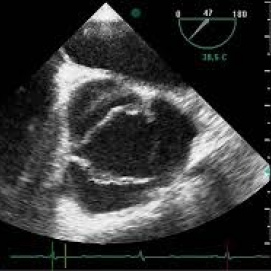

Ecocardiograma de estres con prueba de esfuerzo o con prueba farmacologica. 881210 Idime